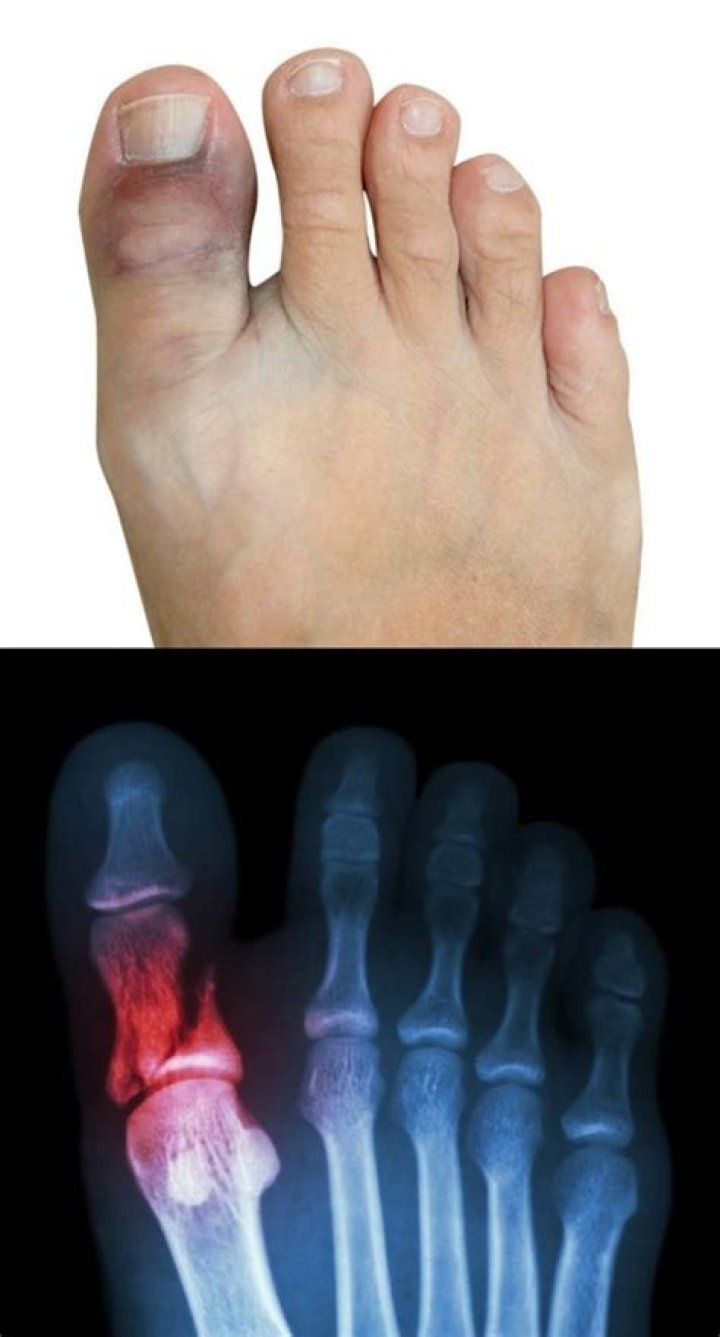

What's a broken toe look like?

Broken Toe Symptoms

Bruising of the skin around the toe may also be noticeable. The toe may not look normal, and it may even look bent or deformed if the broken bone is out of place. It may be difficult to walk because of the pain, especially if the big toe is fractured. Shoes may be painful to wear or feel too tight.

A sprained toe shouldn't look dislocated. It will still swell, but will likely have less bruising. A sprained toe may be painful for several days, but should then begin to improve. One other key difference between a break and a sprain is the location of the pain.

What does a bruised toe mean?

Bruised toes or foot can also be swollen, painful, and often appear purple or blue. A bruised toe can be caused from a broken toe and fracture. A broken foot or ankle can also cause bruises on top of the foot. Read below for more information on causes and treatment options.